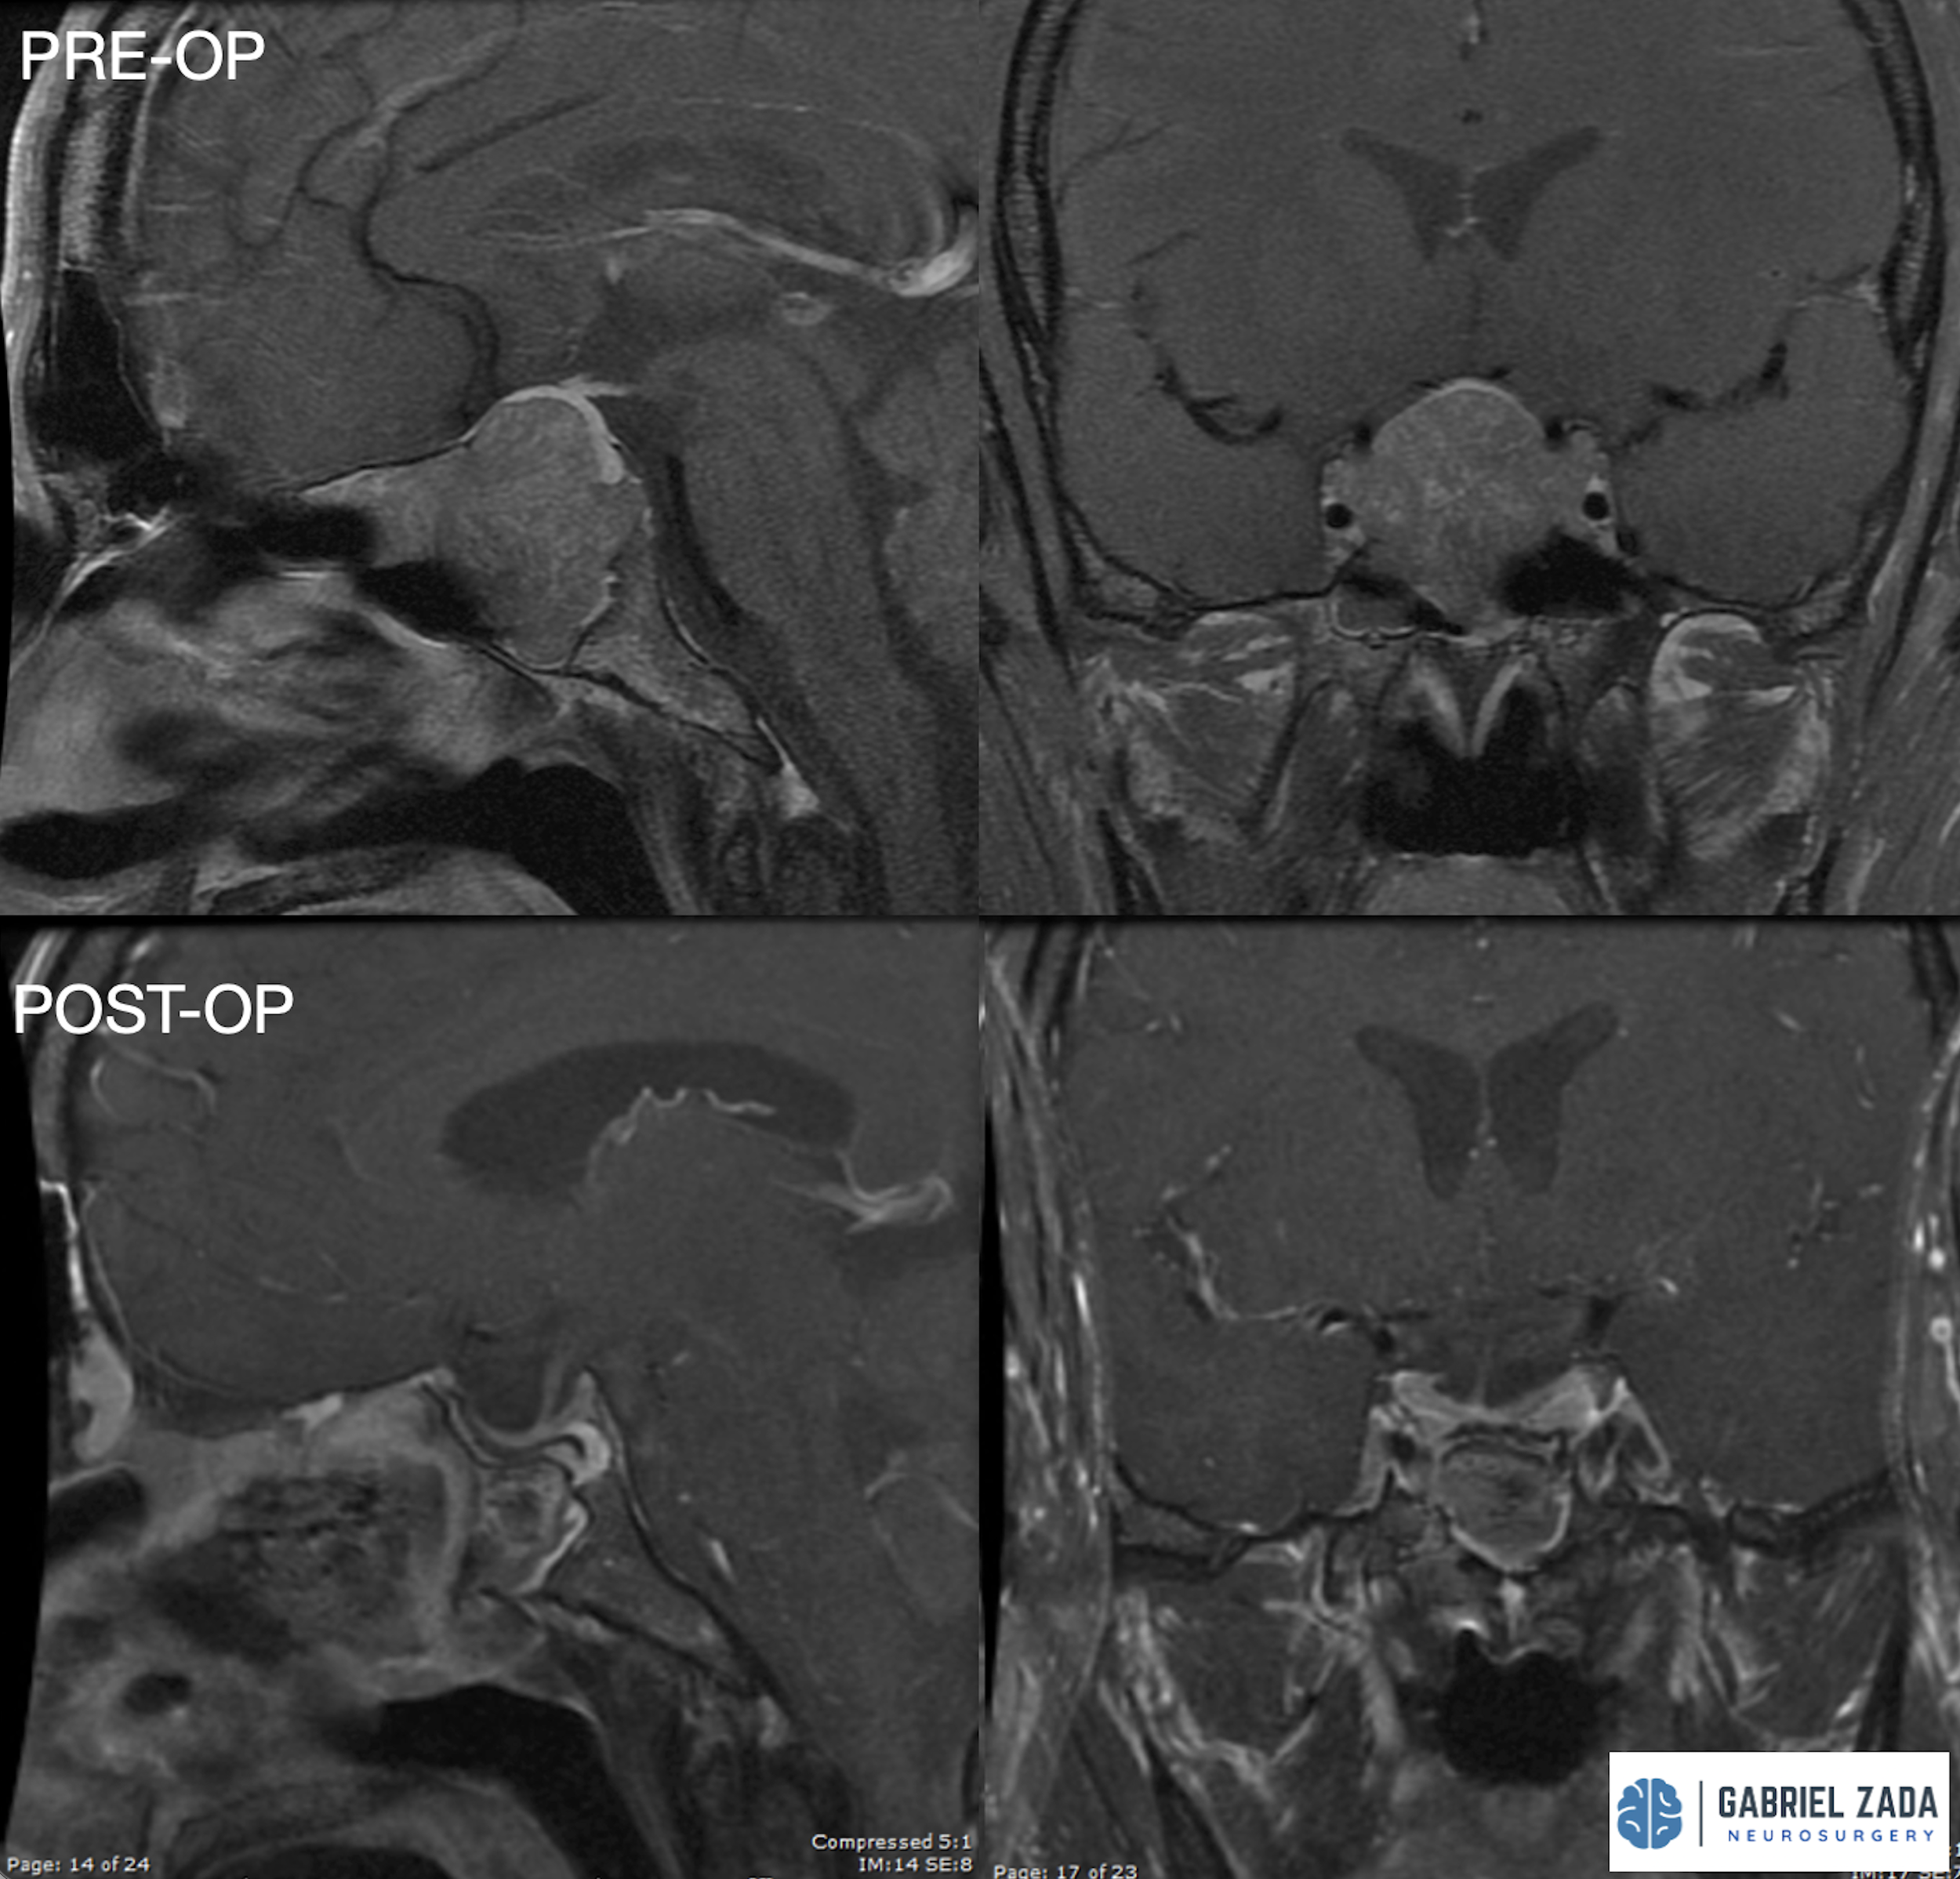

Explore this comprehensive gallery featuring pre‑ and post‑operative imaging of patients with skull‑base tumors treated by Gabriel Zada, MD, MS, FAANS, FACS. These cases highlight Dr. Zada’s expertise in advanced neurosurgical techniques and outcomes.

*Representative cases shown for educational purposes. All images de-identified. Individual results vary.